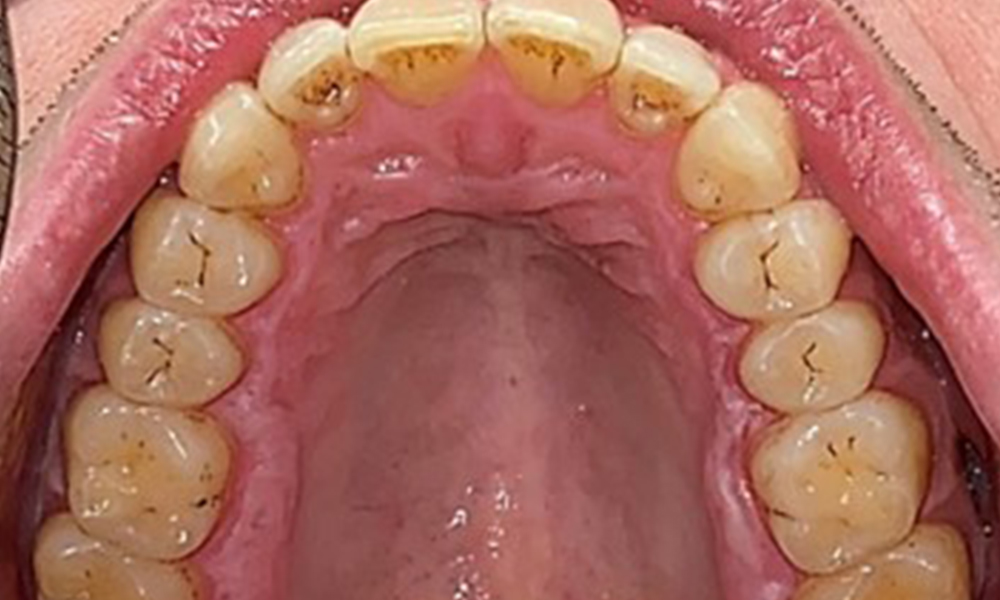

Пациентът има пълно съзъбие с общо 28 зъба. Налице са забележими ерозии и атриции. (Фиг. 4, Фиг. 5). Поради бруксизъм пациентът е носил шина с коригиран блок на захапката през нощта в продължение на много години. Ерозиите са причинени от продължителна консумация на изотонични напитки. Не сe наблюдава загуба на пародонтална кост или активни кариозни лезии.

Наблюдава се пълноценно съзъбие на постоянните зъби без кариес или рентгенологично разпознаваема загуба на кост (фиг. 6). Рентгенологичната загуба на емайл и туберкул е особено видима при 36 и 37.